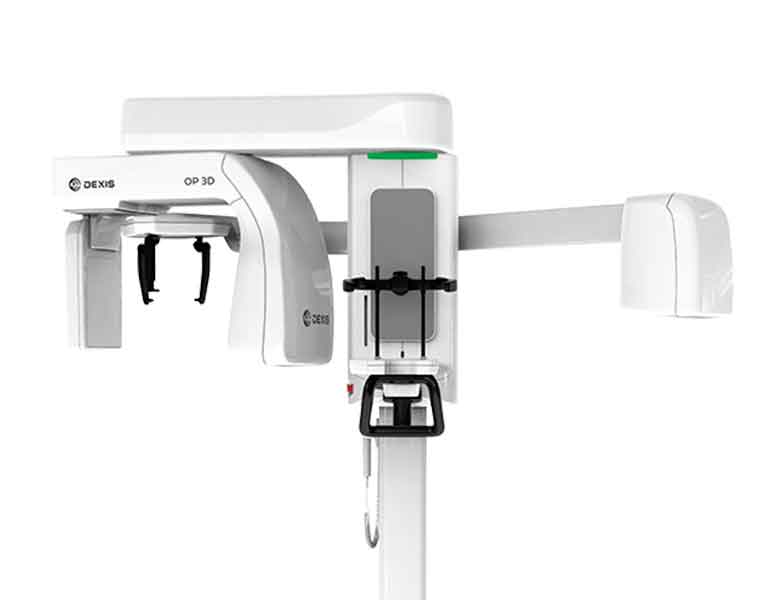

DEXIS オルソパントモグラフ OP 3D LX

DEXIS オルソパントモグラフ OP 3D LXとは

当院では、新しく、歯科用CTとレントゲンの複合機である、次世代型歯科用CT スキャン「DEXIS オルソパントモグラフ OP 3D LX」を導入いたしました。

この機種の導入により、診断機能・診断能力の拡張と、従来よりも短いスキャン時間が可能になり、お体に負担をかけずに、より的確で精密な診断が行えるようになりました。

DEXIS オルソパントモグラフ OP 3D LXの特徴